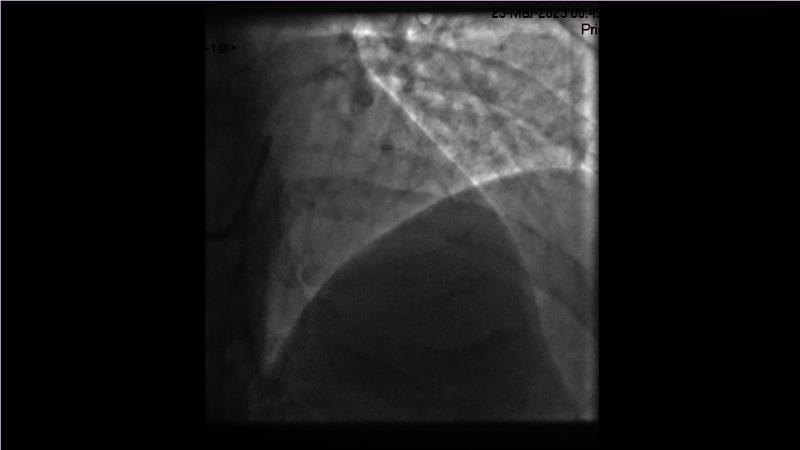

Sirolimus-coated balloon: expanding the scope of indications for complex coronary artery disease treatment

Watch this session to gain case-based insights on using DCBs in complex settings. Learn valuable tips and tricks for optimal DCB application, including the best timing and situations for their use. Discover how to effectively implement a hybrid strategy that combines DES and DCB when needed.